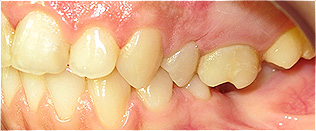

Apinhamento dentário com os dentes caninos em desoclusão (classe II, divisão 2).

![]() |